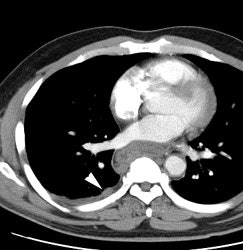

Large laryngeal cancer: The patient shown below had a large laryngeal cancer (white arrows). The PET exam demonstrated very prominent uptake within the mass, but no evidence of metastatic disease.

Large laryngeal cancer: The patient shown below had a large laryngeal cancer (white arrows). The PET exam demonstrated very prominent uptake within the mass, but no evidence of metastatic disease. |